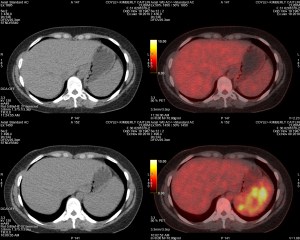

PET Scan Number Two

The Results Are In…Chemo Works